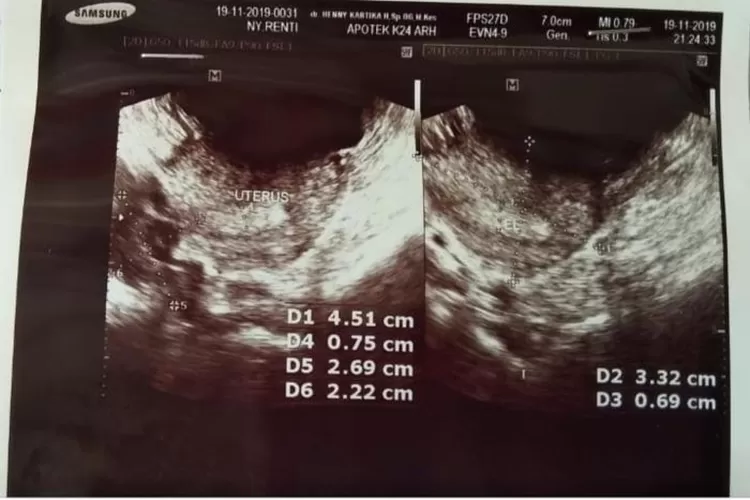

Mengenal Tentang Penyebab Sulit Hamil, Polycystic Ovarian Syndrome (PCOS) (Instagram @rentioktaria/Aspirasiku.id)

Pekan lalu, 20 November 2019, saya mengunjungi klinik praktik dokter kandungan dan diperiksa secara intensif dengan cara USG Transvagina.

Semacam tongkat yang dimasukkan ke dalam tubuh saya melalui vagina, lalu layar besar dihadapan saya muncul gambar 3D hitam putih.

Dokter menerangkan bahwa rahim saya aman, tidak ada miom atau pun kista. Kondisi dinding rahim sangat tipis.

Jumlah sel telur cukup banyak tetapi semuanya berukuran sangat kecil, tidak sesuai standar sel telur perempuan pada umumnya, sehingga menyebabkan saya sulit hamil.